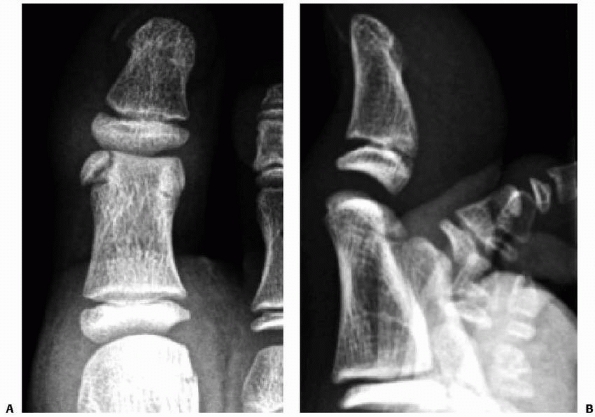

caused by direct trauma or may be due to an underlying osteochondal

preceding trauma as a cause of the defects (Canale and Bedding25 80%, Letts et al.91 79%, Higuera et al.65 63%, and Perumal et al.123 47%). The medial

lesion is usually deeper and cup shaped compared to the thinner “wafer”

type lateral lesion. The lateral lesion is more often associated with

trauma and more symptomatic than the medial lesions. It is postulated

that the medial lesions may be due to more repetitive microtrauma.25,26 Berndt and Harty,12

in 1959, used freshly amputated legs to biomechanically reproduce

injuries to the ankle and observe the injuries inflicted. They showed

that the anterolateral talus hits the medial aspect of the fibula with

dorsiflexion and inversion and that plantarflexion and inversion caused

posteromedial osteochondral lesions (Fig. 27-10).

![]() |

FIGURE 27-11 Adaptation of the Berndt and Hardy12 (1951) classification of osteochondral injuries of the talus by Anderson et al.8

Stage 1 is identified only by MRI scanning, which demonstrates trabecular compression of subchondral bone; stage 2 lesions have incomplete separation of the osteochondral fragment from the talus. If a subchondral cyst also is present, the lesion is designated stage 2a. Stage 3 lesions occur when the fragment is no longer attached to the talus but is undisplaced. Stage 4 indicates both complete detachment and displacement. (From Alexander IF, Chrichton KI, Grattan-Smith Y, et al. Osteochondral fractures of the dome of the talus. J Bone Joint Surg Am 1989;71:1143, with permission.) |